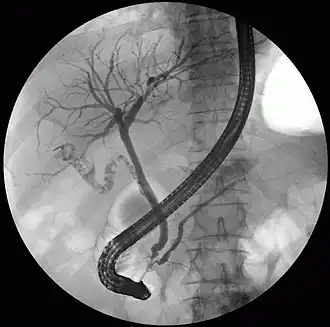

The pancreatic duct or duct of Wirsung (also, the major pancreatic duct due to the existence of an accessory pancreatic duct) is a duct joining the pancreas to the common bile duct. This supplies it with pancreatic juice from the exocrine pancreas, which aids in digestion.

The pancreatic duct joins the common bile duct just prior to the ampulla of Vater, after which both ducts perforate the medial side of the second portion of the duodenum at the major duodenal papilla. There are many anatomical variants reported, but these are quite rare.[2]

Compression, obstruction or inflammation of the pancreatic duct may lead to acute pancreatitis. The most common cause for obstruction is the presence of gallstones in the common bile duct, a condition called choledocholithiasis. Obstruction can also be due to duodenal inflammation in Crohn's disease.[7] A gallstone may get lodged in the constricted distal end of the ampulla of Vater, where it blocks the flow of both bile and pancreatic juice into the duodenum. Bile backing up into the pancreatic duct may initiate pancreatitis.[8] The pancreatic duct is generally regarded as abnormally enlarged if being over 3 mm in the head and 2 mm in the body or tail on CT scan.[9] Pancreatic duct or parts of pancreatic duct can be demonstrated on ultrasound in 75 to 85% of people.[10]